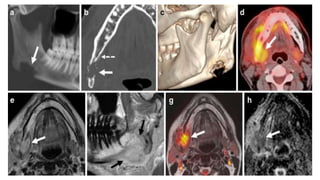

 Benign , locally aggressive tumor

 Origin – Spenopalatine foramen

 C/f – painless progressive unilateral nasal obstruction , epistaxis

 CT – Heterodense mass with avid enhancement , widening of pterygopalatine

fossa, bowing of posterior wall of maxillary sinus (Holman Miller sign), bony

erosion

 Main blood supply – Internal maxillary artery, branch of ECA , others – ascending

pharyngeal , palatine

 Treatment – Preop Embolization – Surgical resection